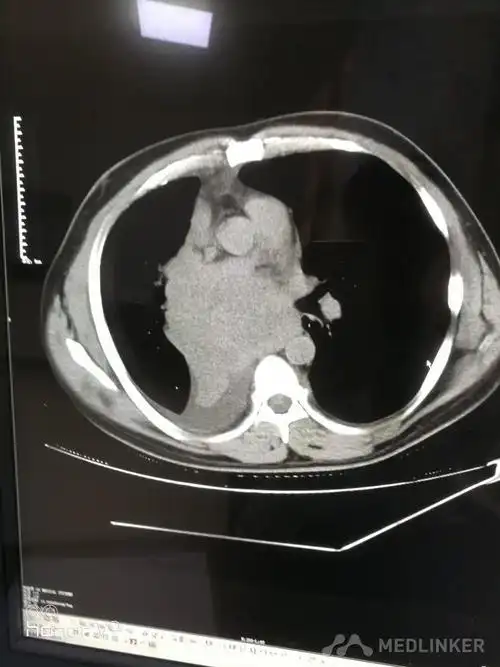

ct诊断中央型肺癌伴心脏转移一例

中央型肺癌肺内多发转移一例!

右肺中央型肺癌

中央型肺癌一例直接征象和间接征象都有哪些

简述中央型肺癌特点及影像表现